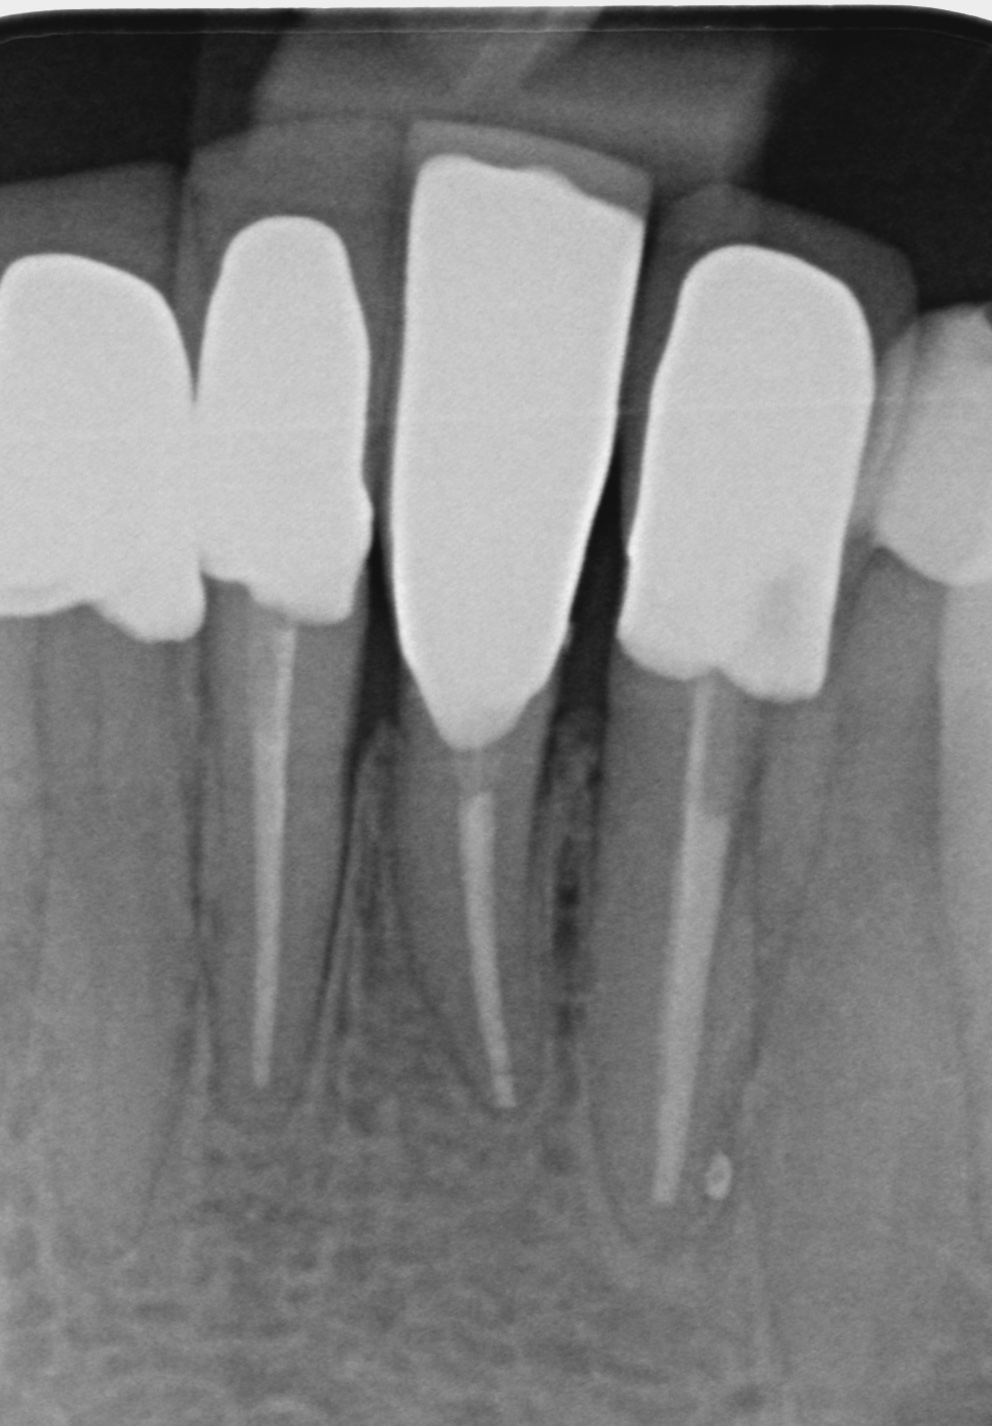

Fallbeispiele

Zum Vergrössern klicken